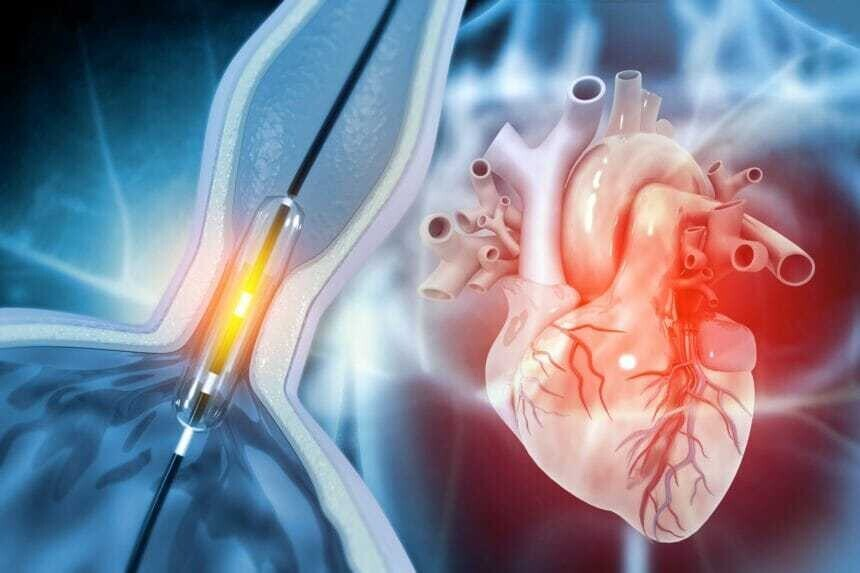

В ходе проведения манипуляции выполняют прокол вены для введения катетера, который приближается к исследуемому органу. Ход катетера постоянно контролируется специалистом. Контрастное вещество поглощает рентгеновский лучи и позволяет сформировать четкую картину сосудов сердца на мониторе.

- Далее выполняют прокол кровеносного сосуда для введения катетера, который хирург постепенно продвигает к устью артерии. После достижения нужного участка в катетер подается контрастное вещество, достигающее сосудов сердечной мышцы.